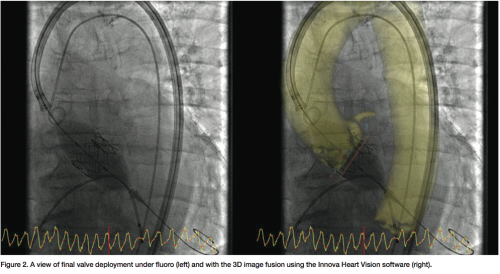

In our institution, the 3D imaging is a reconstruction based on a computed tomography (CT) scan. One may also do 3D angiography with Innova 3D. By visualizing the anatomy in 3D, we cannot only plan out our procedure, but also locate the coronary ostium, and assess the aortic valve plane and the iliac artery lumen diameter. We also use 3D imaging to guide the procedure, because once the patient’s anatomy from the groin to the aortic valve is assessed with 3D imaging, a 3D reconstruction can be fused to regular fluoroscopic imaging. This fused image will follow any table panning or gantry angulations that are changed throughout the procedure. To minimize the difference between the fluoro image and the 3D model, we may also utilize the ECG-gated and Image Stabilization functions. We find it a great help for valve analysis and assessment, device plane assessment, and valve delivery.

Three-dimensional imaging in TAVR will be very important for experienced interventional cardiologists, but also for people who are entering the learning curve for this procedure. Physicians will feel themselves more confident if they have software that helps to accurately place and deploy valves in the right position. The integration of the 3D image in the procedure workflow was seamless. A single GE workstation provides very comprehensive tools for the case preparation and once ready, the image fusion is initiated by a simple click with display in the exam room. Any specific tuning, such as image contrast between the fluoro and 3D image in the fusion, can be performed from tableside.